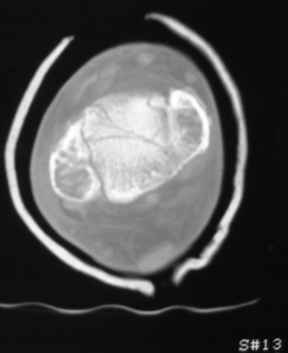

Остеопороз (продолжение 3) - данные КТ

Продолжая тему представляю данные КТ нашей пациентки.

Вопросы к сообществу - в сообщении №2.

Юрий Алексеевич Булахтин